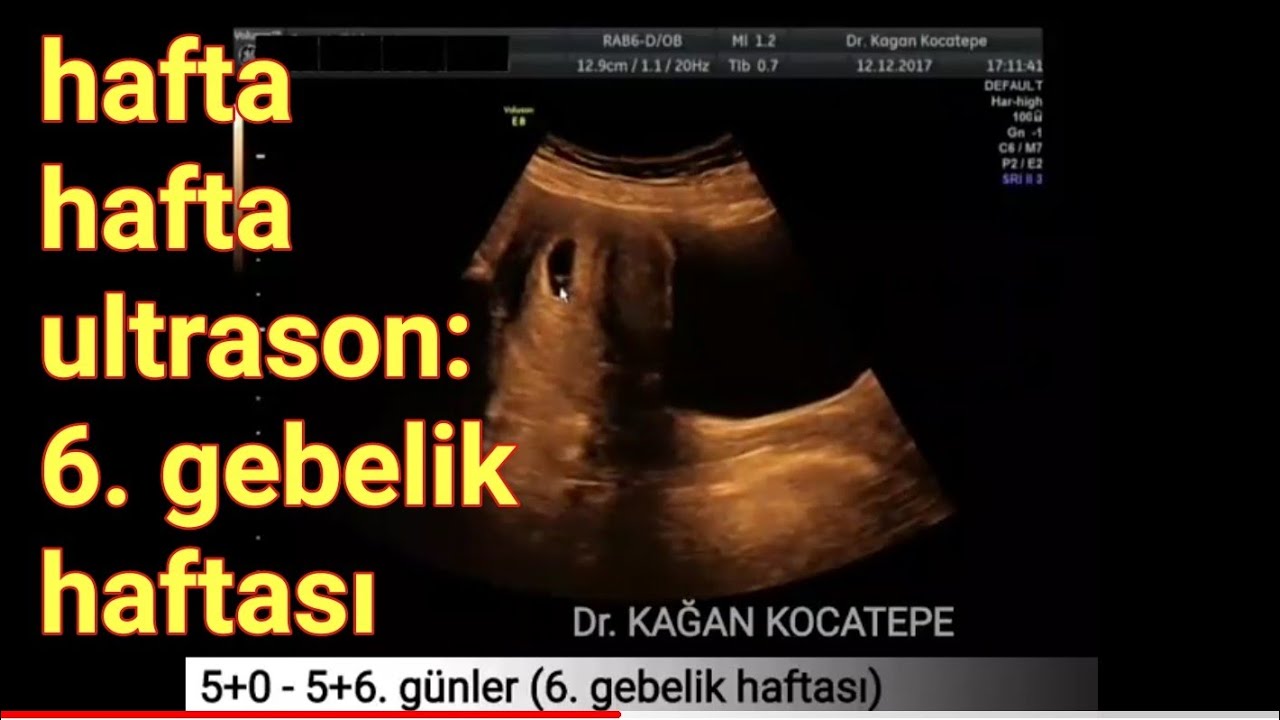

Bebeğin ileride kol ve bacaklarını oluşturacak tomurcuklar şimdiden belirginleşmeye başlar. Bebeğin kalbi bu dönemde vücudun büyük çoğunluğunu kapsar. 7 haftalik gebeli̇k (hami̇leli̇k) görüntüsü. Hamilelik macerasının ilk ayları olan 6 haftalık gebelik, bazı kadınlar için hamilelik müjdesinin yeni alındığı, kimi kadınlar içinse heyecanların yeni başladığı bir dönemdir.hamilelik teşhisi konulmuş ise, gidilen ultrason muayenesinde bebeğin kalp atışları bu hafta içinde rahatlıkla duyulabilir. 6 haftalık gebelikte bebeğin ultrason görüntüsü gebelikte 6 haftalık bebek görüntüsü. Ultrason, 6 ile 8 haftadan sonra çoğul gebeliği anlamak için hatasız sonuçlar verir. 6 haftalık ultrason görüntüsü erken gebelik belirtileri (merhaba, sabah bulantısı !) tam etkilerini hissediyor olabilirsiniz, ancak iyi haber şu ki, yakında bebeğinizin yüzü. Hamileliğini öğrenen anneler, ultrasonda bebeğini görmek için büyük bir istek duyabilir. Bebeğin ileride kol ve bacaklarını oluşturacak tomurcuklar şimdiden belirginleşmeye başlar.

Hamileliğini öğrenen anneler, ultrasonda bebeğini görmek için büyük bir istek duyabilir. Beyin, omurga, büyük damarlar, göz ve barsak, böbrek, karaciğer gibi organlar gelişmeye başlamıştır. Altı haftalık gebelikte bebeğin kalp atışları rahatlıkla ultrason muayenesinde duyulabilir ve görülebilir. Evet, 6 haftalık hamilelikte doktorunuz gebelik kesesi içinde bebeğe ait kabartıyı görebilir. Haftasında bebeğin başı ile vücudunun kalan kısmı yaklaşık aynı büyüklükte görünmektedir. Bebeğinizin kalbi 2 mm boyutuna ulaşmış ve aktif bir şekilde çalışıyordur.

Bu döneme kadar temel haliyle oluşmuş olan dolaşım sistemi artık bebeğinizin kalbine kan pompalamaya başlar. Bebeğin beyni gelişmeye ve aktivite göstermeye başlamıştır. 6 haftalık gebelikle beraber anne karnındaki bebekte çeşitli değişimler meydana gelir. Gebelik testi pozitif çıkan kadınlarda 5 veya 6. Hafta arka kısım ön bölgeden daha hızlı gelişim. Eğer doğurganlık tedavileriyle hamile kaldıysanız, aşılanan embriyoların sayısını görmek için daha erken, yani yaklaşık ilk 8 hafta içinde ultrasona alınırsınız.

Eğer doğurganlık tedavileriyle hamile kaldıysanız, aşılanan embriyoların sayısını görmek için daha erken, yani yaklaşık ilk 8 hafta içinde ultrasona alınırsınız. Bebeğin beyni gelişmeye ve aktivite göstermeye başlamıştır. 6 haftalık gebelik kesesi ultrason görüntüsü 6 haftalık gebelik belirtileri. 6 haftalık gebelik kesesi bazen görülmeyebilir, bu durumda vajinal ultrason muayenesi yapılabilir. 6 haftalık gebelikte ultrason görüntüsü, her ne kadar yalnızca küçük bir noktadan oluşsa da gebelik hakkında çok önemli bilgiler verir. 6 haftalık bebek ultrason görüntüsü.

Ultrason, 6 ile 8 haftadan sonra çoğul gebeliği anlamak için hatasız sonuçlar verir. Haftası nda ultason ile bebeğinizin görüntüsünü görebilir, kalp atış sesini duyabilirsiniz. Evet, 6 haftalık gebelik kalp atışı duyabileceğin özel haftalardan birisi.

7 haftalik gebeli̇k (hami̇leli̇k) görüntüsü. 6 haftalık gebelikte ultrason görüntüsü, her ne kadar yalnızca küçük bir noktadan oluşsa da gebelik hakkında çok önemli bilgiler verir. Haftası nda ultason ile bebeğinizin görüntüsünü görebilir, kalp atış sesini duyabilirsiniz.

6 haftalık ultrason görüntülerinde (6 haftalık bebek görüntüsü anne karnında) bebeğin resminden pek birşey anlamayabiliriniz ancak aşağıdaki resimde bebeğin başından en ucuna giden kıvrımlı bir yapı göreceksiniz. Genel olarak 6 haftalık görüntülerde bebeğin vücut siması, akciğeri, oldukça minik el yapısı da görülmeye başlanabilir. Hafta bitimindeki kontrolünüzde gebelik keseniz ultrasonda kesin olarak görünecek hatta kesenin içerisinde, ileride bebeğiniz olarak kucağınıza alacağınız canın yavaş yavaş.

Bu haftada embriyonun organlarının çoğunun oluşumu başlar, bu nedenle bebeğin. Anne adayları tarafından sıklıkla merak edilen sorulardan biri 6 haftalık bebek kaç mm olur şeklindedir. 6 haftalık bebek görüntüsü 6 haftalık bebek ultrason görüntüsü embriyonun 3 ila 5 mm boyutlarında olduğu bilgisini edinmenize olanak tanır.

6 haftalık bebek ultrason görüntüsü. Hamilelik macerasının ilk ayları olan 6 haftalık gebelik, bazı kadınlar için hamilelik müjdesinin yeni alındığı, kimi kadınlar içinse heyecanların yeni başladığı bir dönemdir.hamilelik teşhisi konulmuş ise, gidilen ultrason muayenesinde bebeğin kalp atışları bu hafta içinde rahatlıkla duyulabilir. Bu hafta bebek kese içinde çok küçük bir nokta olarak görülebilir.

6 haftalık gebelikte bebeğin ultrason görüntüsü üst resimdeki gibidir. Haftası nda ultason ile bebeğinizin görüntüsünü görebilir, kalp atış sesini duyabilirsiniz. Altı haftalık gebelikte bebeğin kalp atışları rahatlıkla ultrason muayenesinde duyulabilir ve görülebilir.

Memelerde hassasiyet, sık idrara çıkma isteği, mide bulantıları, kokulara hassasiyet gibi durumlar ilk haftalarda oldukça normal karşılanır. Bebeğin ileride kol ve bacaklarını oluşturacak tomurcuklar şimdiden belirginleşmeye başlar. 6 haftalık ultrason görüntülerinde (6 haftalık bebek görüntüsü anne karnında) bebeğin resminden pek birşey anlamayabiliriniz ancak aşağıdaki resimde bebeğin başından en ucuna giden kıvrımlı bir yapı göreceksiniz.

6 haftalık bebek görüntüsü 6 haftalık bebek ultrason görüntüsü embriyonun 3 ila 5 mm boyutlarında olduğu bilgisini edinmenize olanak tanır. 6 haftalık gebelikte bebek gelişimi ile ilgili olarak gözler oluşmaya başlar ve kolların ve bacakların ana hatları belirir; Bebeğin solunum ve sindirim sistemini oluşturacak ilk yapılar belirginleşir.

6 haftalık gebelik ultrason görüntüsü nasıldır? Gebeliğin altıncı haftasında hızla büyümeye devam eden bebeğin anne karnındaki görüntüsü netleşmeye başlar. Eğer doğurganlık tedavileriyle hamile kaldıysanız, aşılanan embriyoların sayısını görmek için daha erken, yani yaklaşık ilk 8 hafta içinde ultrasona alınırsınız.

Haftasında bebeğin başı ile vücudunun kalan kısmı yaklaşık aynı büyüklükte görünmektedir. 6 haftalık gebelikte ultrason görüntüsü, her ne kadar yalnızca küçük bir noktadan oluşsa da gebelik hakkında çok önemli bilgiler verir. Bebeğin beyni gelişmeye ve aktivite göstermeye başlamıştır.